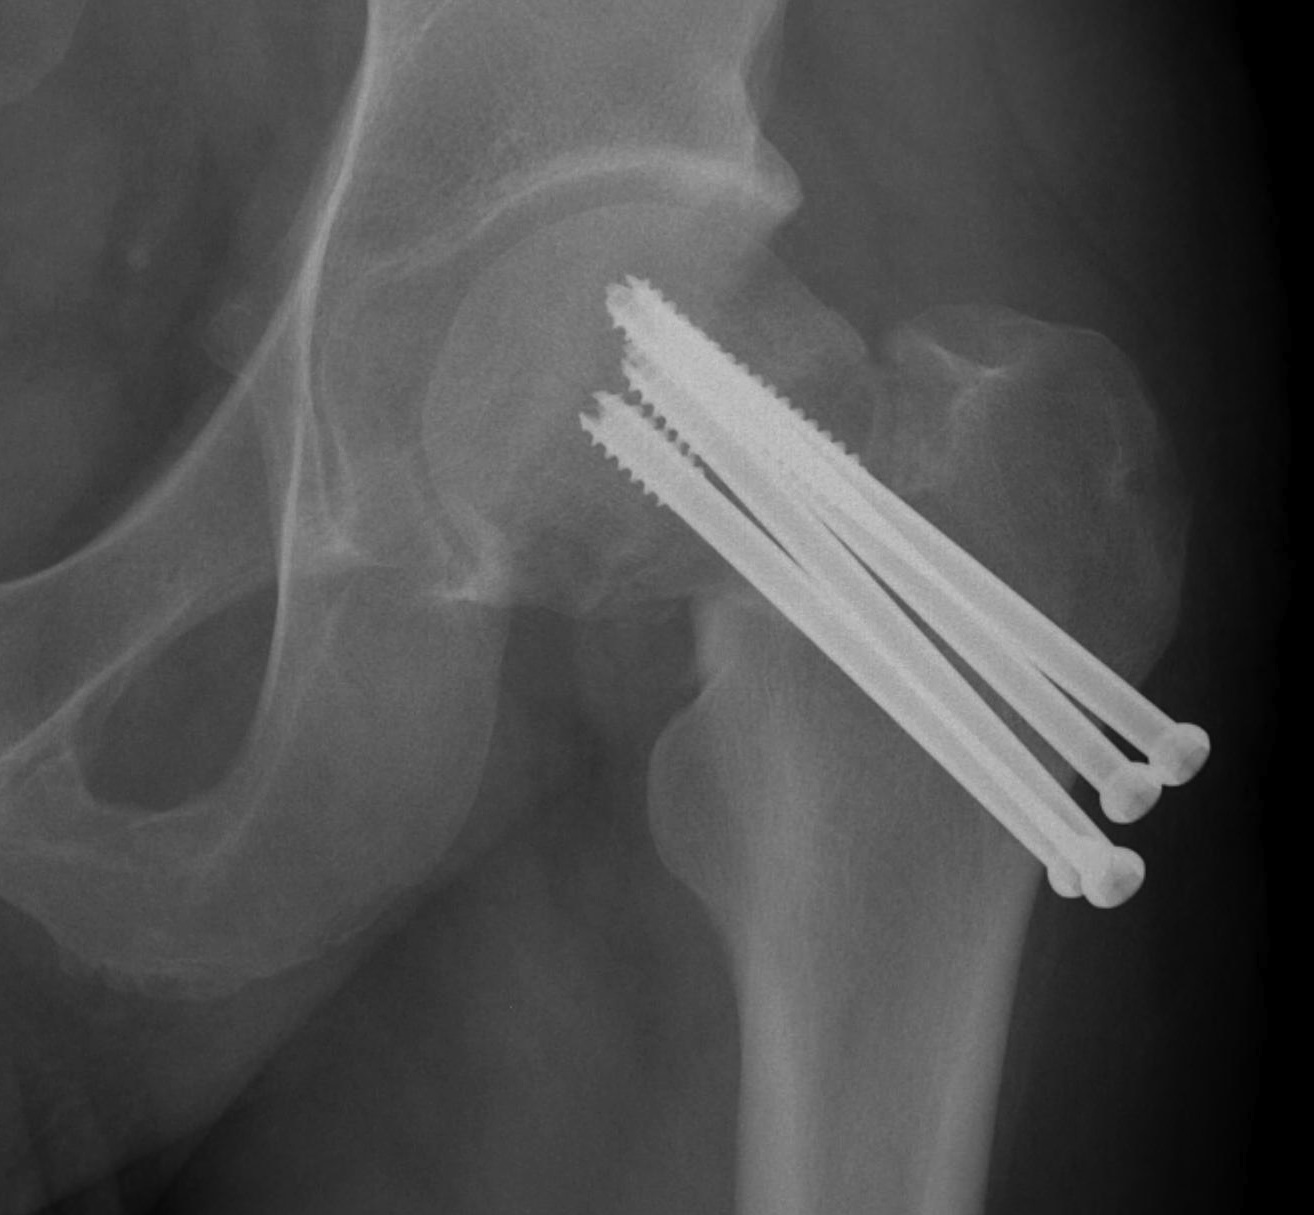

Cannulated screws

Technique

- 3 screws

- ensure inferior screw entry point is above lesser trochanter to prevent fracture

- ensure threads cross fracture site entirely to obtain compression

- need correct screw length so screw head can compress against cortex